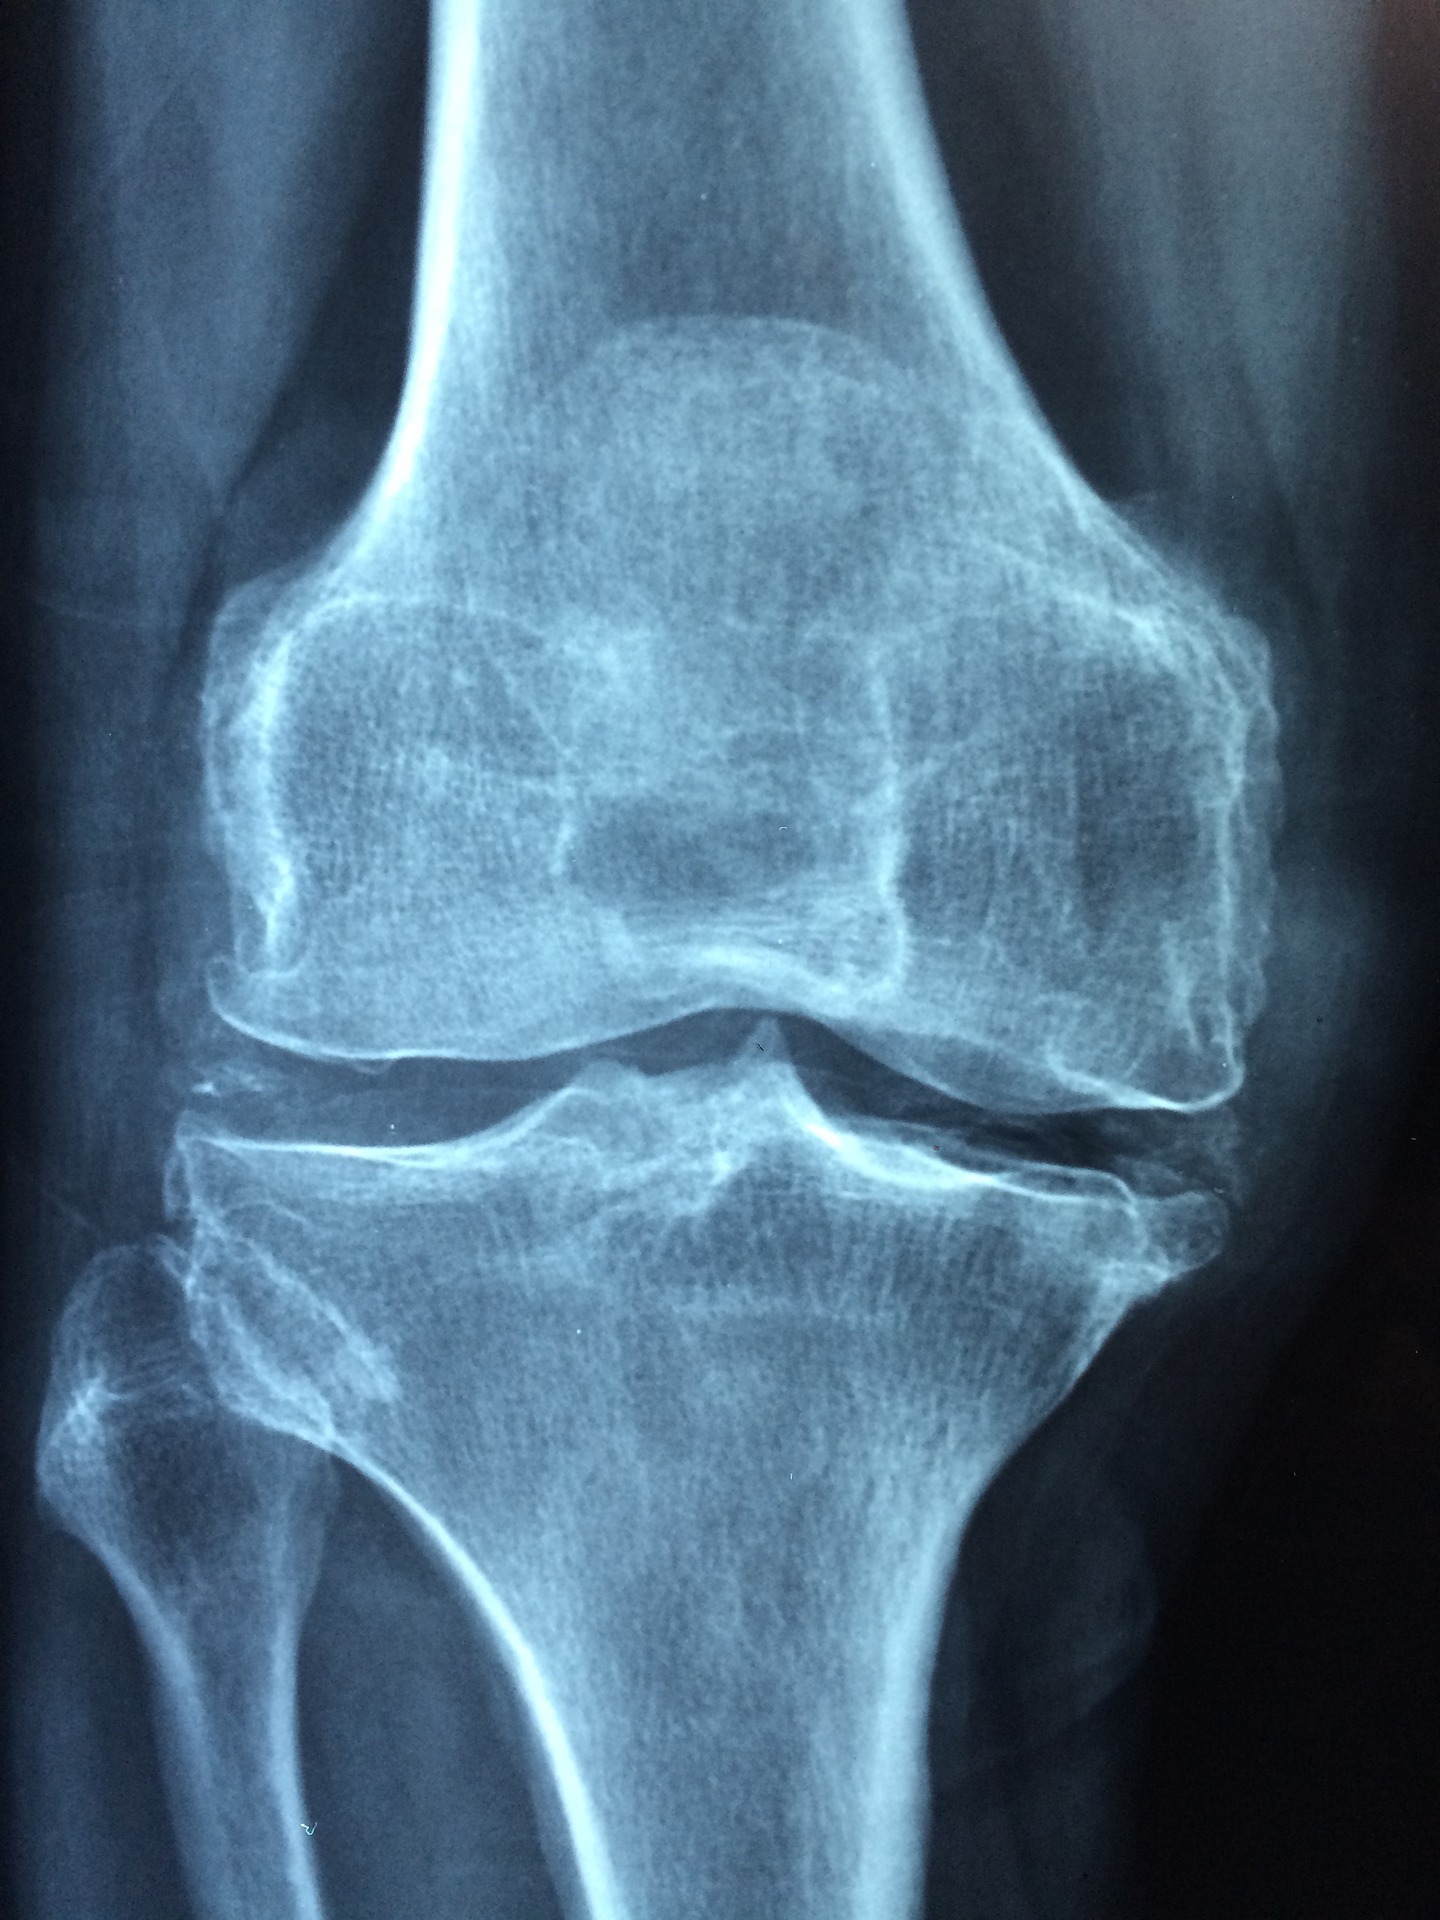

The overarching requirement to participate in the MDL is (1) to prove implantation of the Zimmer NexGen knee components (with product stickers from the original surgery), and (2) to show through the medical records clear evidence of loosening. Loosening is when the artificial knee components begin to move in the patient’s leg and separate from the bone. This is not good. Loosening can be very painful. A loose artificial knee will cause major complications and eventually require replacement and revision surgery. When a patient complains to an orthopedic surgeon about knee pain after a total knee arthroplasty, the doctor will order an X-ray. The doctor will look for radiolucent lines, which are spaces between the artificial knee component and the patient’s bone. Essentially, small gaps occur because the medical device is not implanted tightly or securely to the bone. These spaces can cause serious problems for a patient with an artificial knee, and can be the first signs of an artificial knee failure. The spaces often fill with fluid or tissue which can cause additional loosening of the medical device.